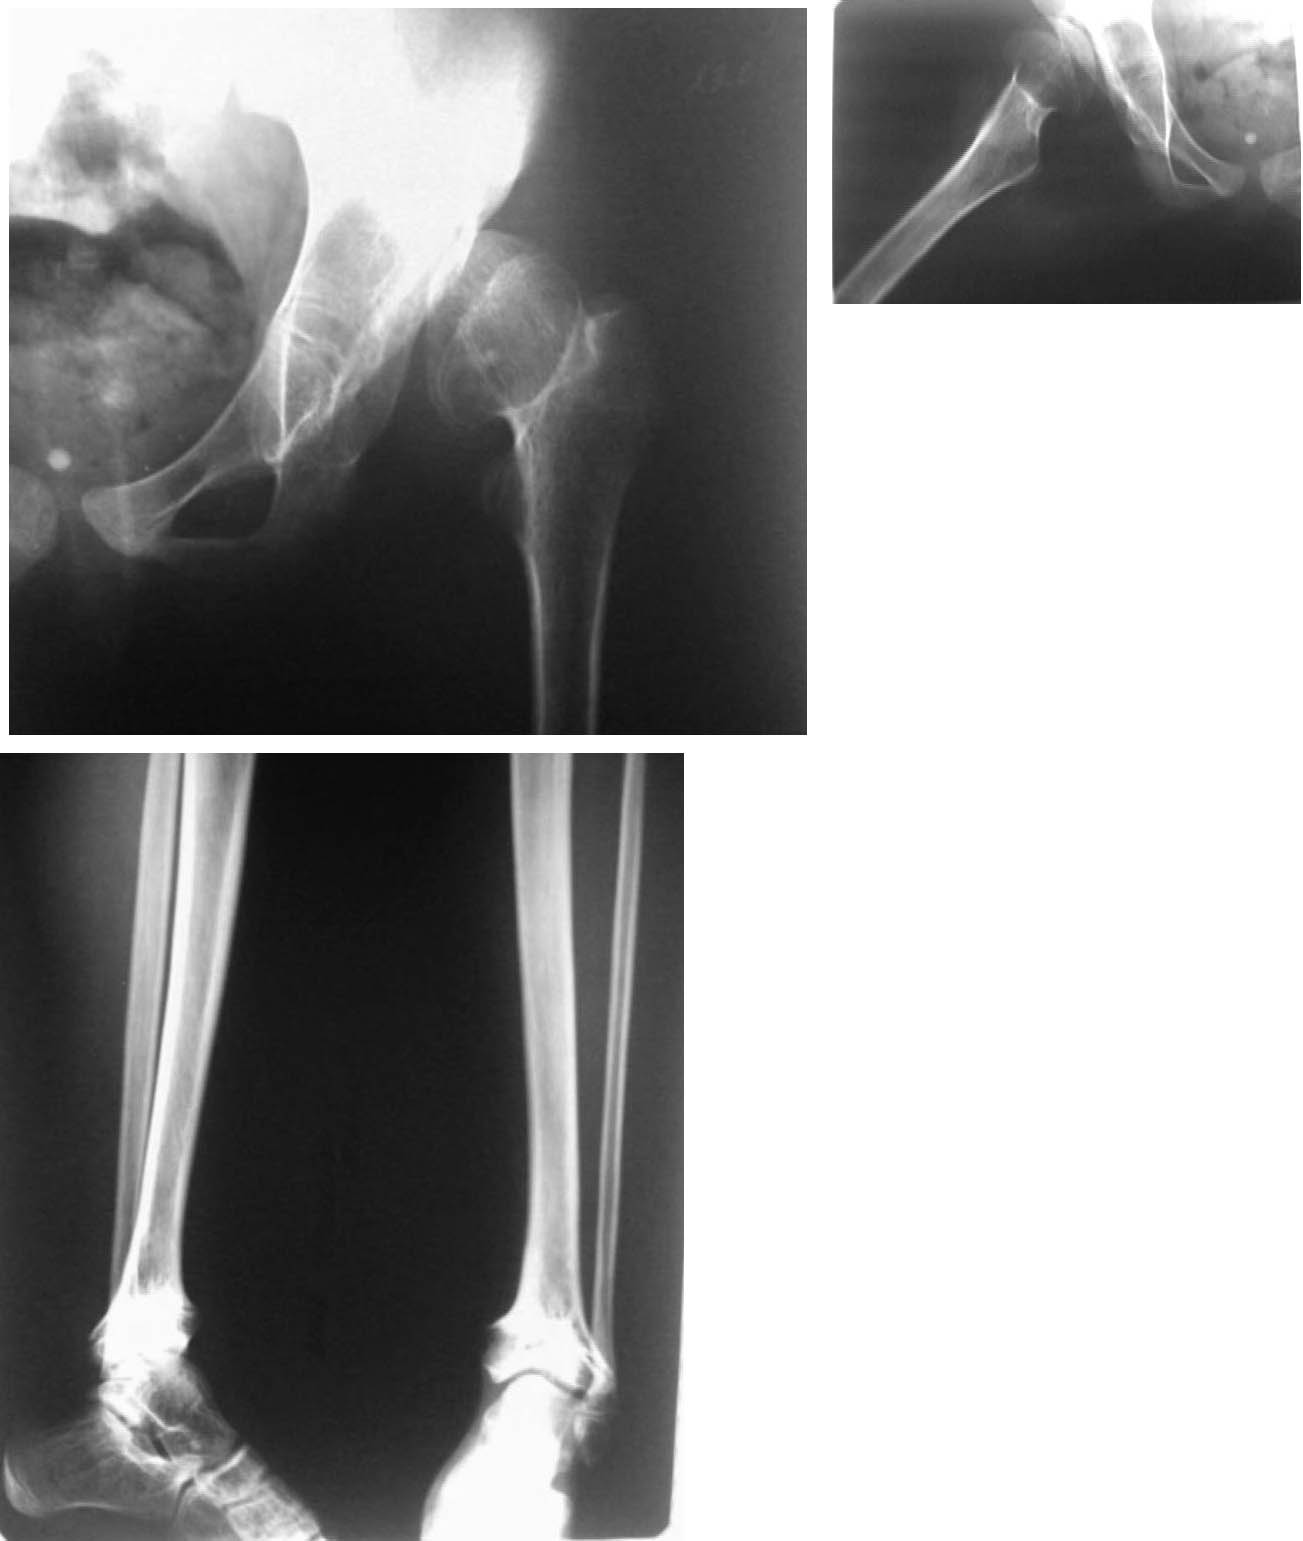

У моей дочери врожденный вывих ТБС.

На данный момент ей 12 мес.

С 3-Х месяцев мы были 4 мес в стременах и месяц в аппарате.

После (2.11.10) назначения на вытяжку с закрытым вправлением под наркозом. Мы незамедлительно легли в больницу. Дочь проходила в гипсе 2 месяца после вправления.

17.01.11 мы его сняли и одели аппарат. На данный момент ребенок находится в аппарате. А также сделали ренген.

Я вас очень прошу, прокоментируйте рентген(рентген сделан в аппарате). Также 14.02 сделали узи. За месяц появились ядра окостенения.

в аппарате, после снятия гипса.jpg

340KB (349175 bytes)